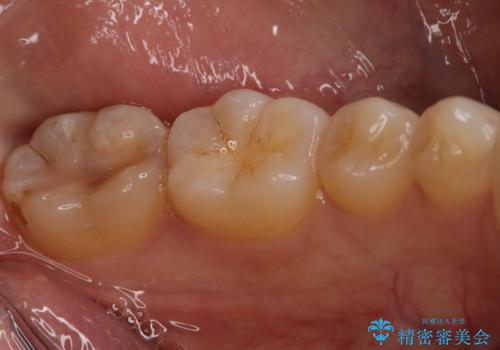

- 左下6、7番の虫歯をセラミックにて治療を希望された患者様です。

切削量を考慮してセラミックインレーを選択しました。

- 154,000円(2本分)費用は治療当時の料金となります

7番は虫歯が深かったのでCR裏層した上で形成、印象をしています。